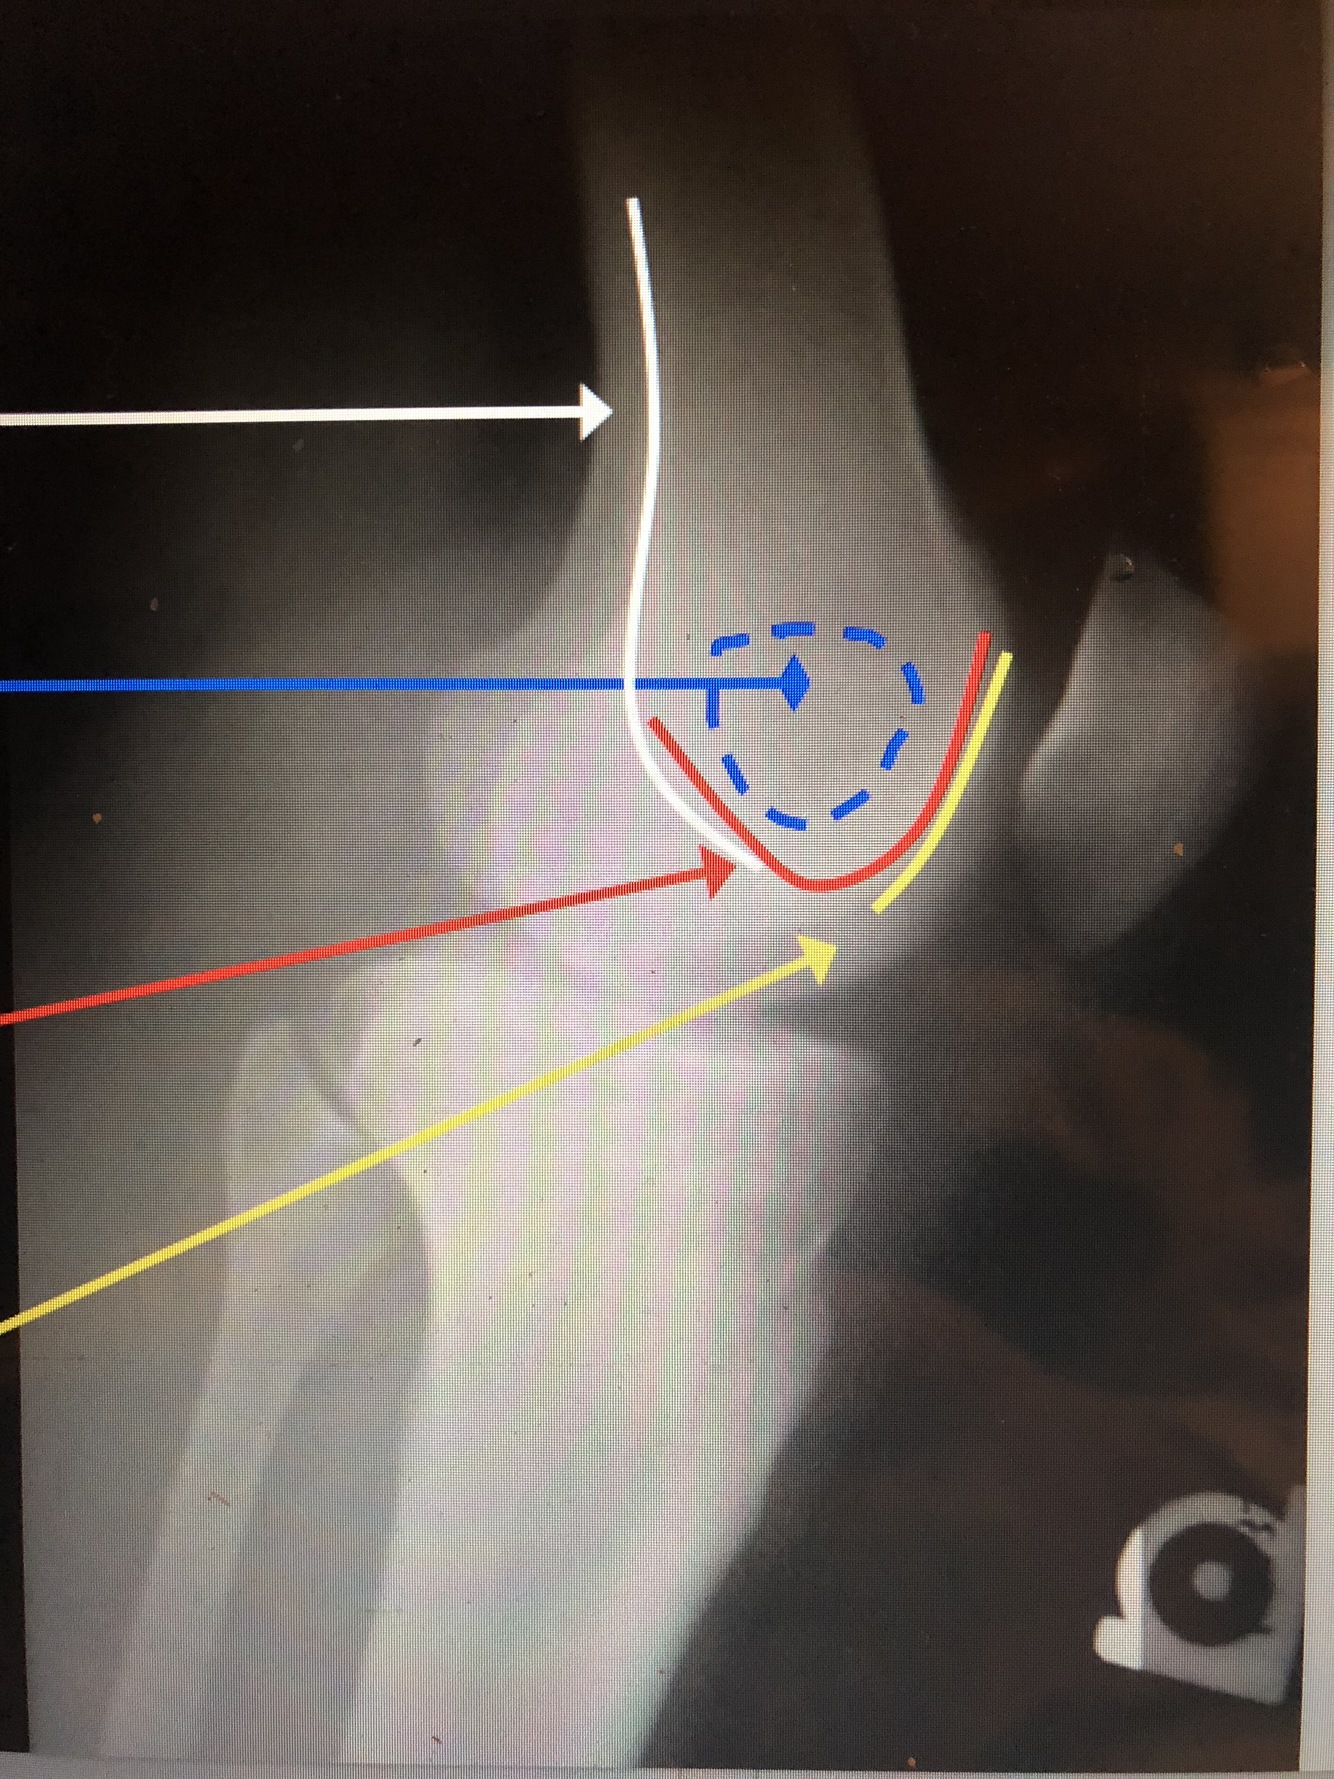

What is the white line?

Popliteal Surface of the Femur

What is the blue dotted lines?

Ludloff’s Spot – area of lucency in condyles

What is the red line?

Intercondylar Notch/Groove

Q

Patellar Surface of the Femur

What is the red dotted line?

patella